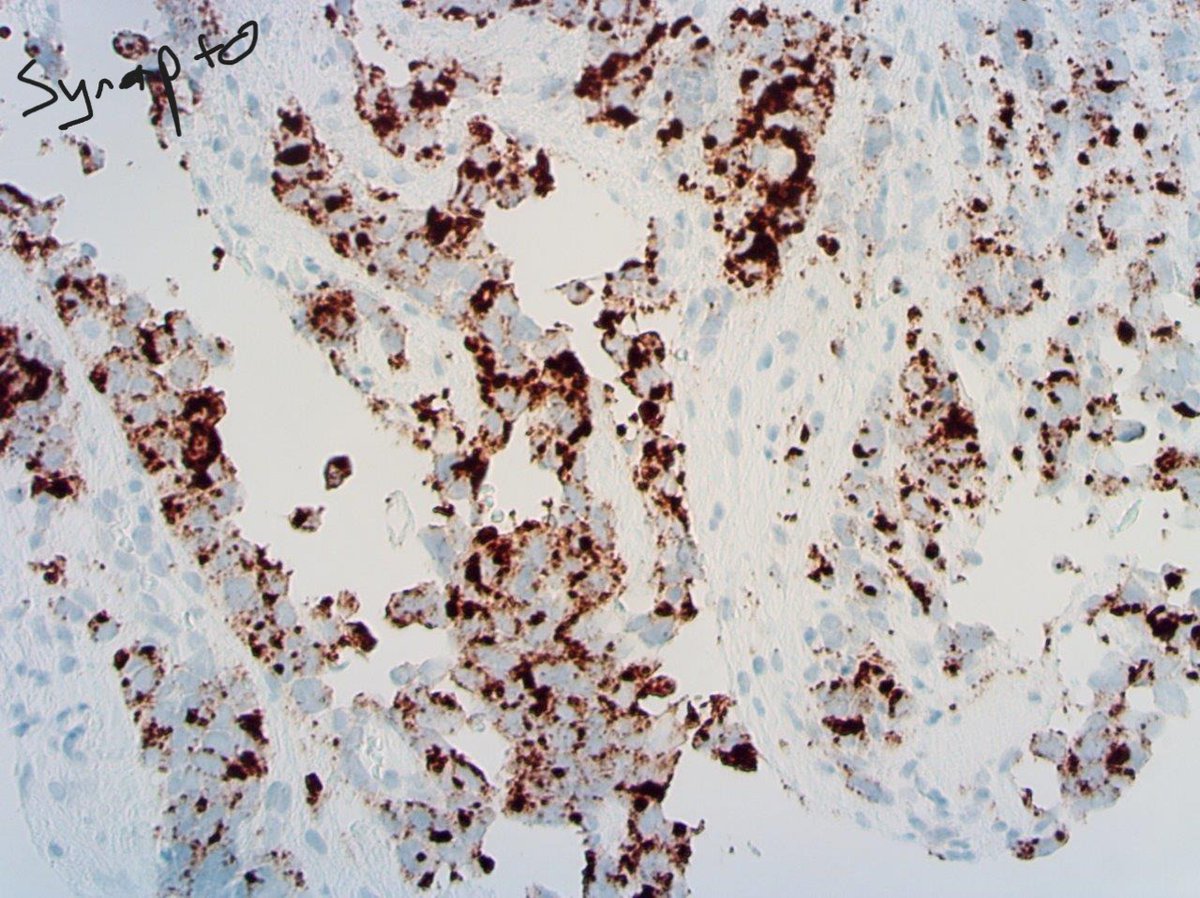

1/2. High grade "small round blue cell" sinonasal malignancy in an adult male. Cytokeratin dot positive, synatophysin and CD56 also positive with Ki67 >90% #PathTwitter

1/2. High grade "small round blue cell" sinonasal malignancy in an adult male. Cytokeratin dot positive, synatophysin and CD56 also positive with Ki67 &gt;90% #PathTwitter